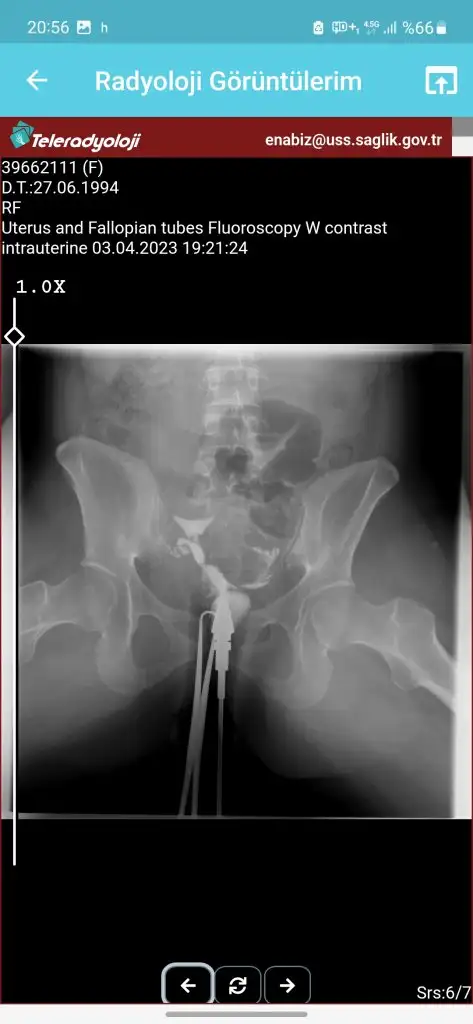

tüp bebek merkezine yönlendirdi . Orada daha detaylı kan tahlili muayene yapıldı adet bitimi hsg çekindim . Çekindiğim gün işlem başında doktor iki tüpün de tıkalı canım dedi ben ağlamaya başladım ağlama sakinleş ilaç ile açmaya çalışacağım eğer olmazsa ameliyat olursun demişti . İşleme 4-5 kez tekrarladık . Sonra iyi kötü bi gidiş oldu . O zaman ki ilgilenen doktora olanları anlattım böyle birşey imkansız tüpler açık o ara kasmışsındır dedi ama hiç kasmadım inanın ki . 6 ay dene olmazsa gel dedi 6 ay sonra gittim o doktor yoktu . Başka doktora geçtim oda sızıntının yeterli olmadığını hala tıkalı olduğunu ve içeriye iyi bir müdahale yapılması gerektiğini söyledi . Ameliyat önerdi . Laparoskopi olacağım ayın 27 sinde . Sonrasında aşılama yapmaya başlıcaz olmazsa